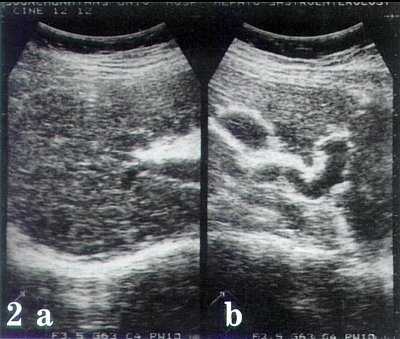

Рис. 2. Эхограммы больного циррозом печени и портальной гипертензией.

a) Повышение эхогенности и неоднородная структура печеночной паренхимы с наличием узлов.

b) Видна расширенная пупочная вена.

На эхограмме в левой косой проекции (рис. 1) визуализируются диффузные гиперэхогенные включения (точечные кальцификаты) в селезенке, состоящие из телец Гамна-Гэнди. При сканировании в правом подреберье (рис 2b) визиализируется печень повышенной эхогенности, с неоднородной структурой, образованием узлов в ее паранхиме и расширением пупочной вены.